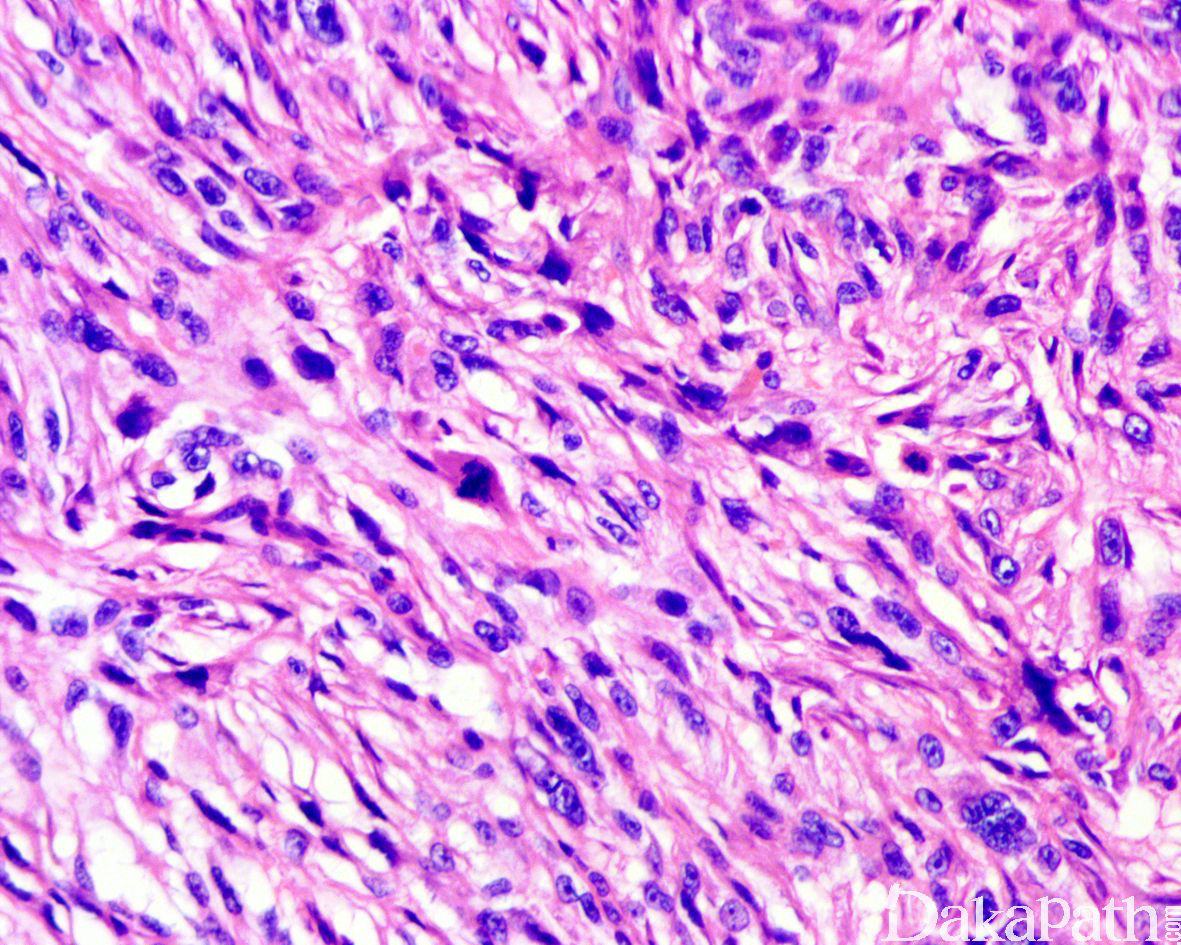

肿瘤富于细胞,由非典型梭形细胞和多形性的上皮样细胞组成,比例多少不等,可见杜顿型或破骨样巨细胞,呈弥漫片状或交织束状以及席纹状排列;瘤细胞胞浆丰富,嗜酸性或浅染,核多形性明显,染色质空泡状,可见多个核仁,核分裂象活跃(平均 20 个/10HPF),常见非典型核分裂象;

半数以上可见肿瘤性坏死,25%分别可见神经浸润和血管/淋巴管浸润;